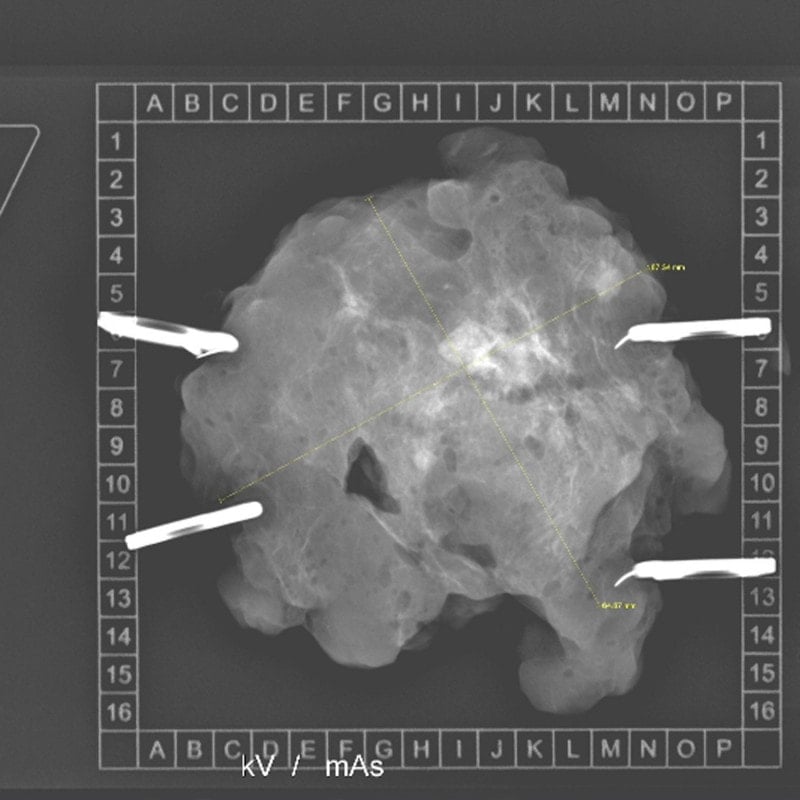

The KLINITRAY™ Mammary Plates from Klinika Medical are an ideal tool in breast cancer surgery. They serve as a transport and x-ray system for tissue, allowing tumour fixation. The lightweight plastic tray is equipped with orientation markers and a coordinate frame and is highly visible in X-rays. This ensures precise localization of the tumour within the tissue sammple.

The KLINITRAY™ Mammary Plates are suitable for both radiological and sonographic examinations. Surgeons can securely affix tissue using specialized safety pins, maintaining stability in a defined 3D topographic orientation. This secure fixation allows for easy transportation of the tumour tissue. Precise definition of the free resection margin enables safe examination and preparation. They are suitable for both intraoperative and postoperative cases and are available in various sizes tailored for the left or right breast side.

- Lightweight plastic tray with orientation markers and coordinate frame

- Highly visible in X-rays

- Precise definition of the free resection margin

- Clear lesion localization with x-ray visible orientation markers